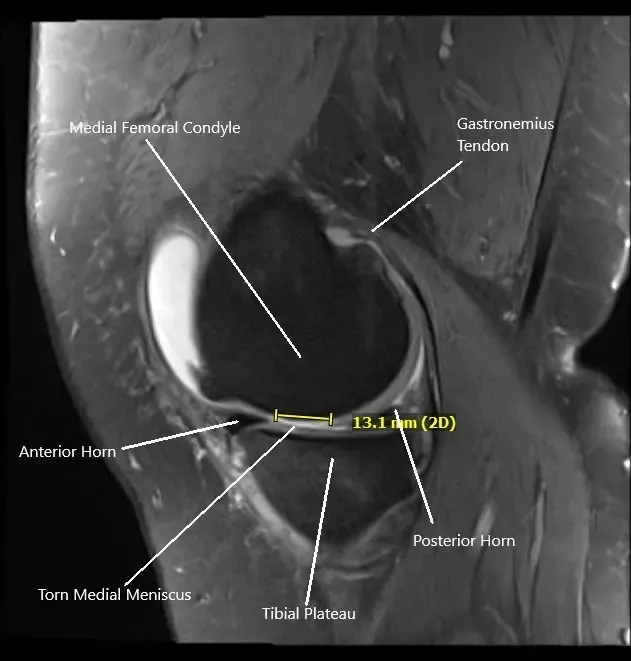

Resonancia magnética de la rodilla derecha en sección sagital que muestra desgarro del menisco medial

La resonancia magnética de la rodilla derecha sugirió un desgarro complejo del cuerno posterior del menisco medial, fractura por estrés subcondral tibial y artrosis patelofemoral severa. Debido al fracaso del manejo conservador, se recomendó al paciente el manejo quirúrgico. Los riesgos, beneficios y posibles complicaciones se discutieron en profundidad con el paciente. Los pacientes aceptaron seguir adelante con el procedimiento.